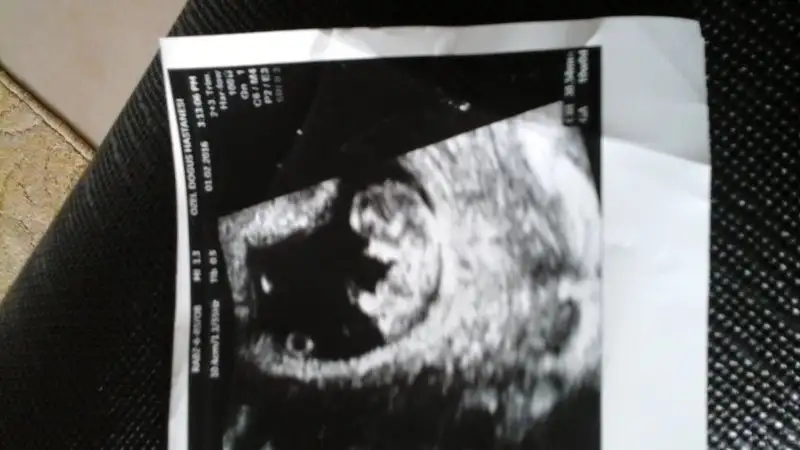

selam hepinize.. doktordan geldim. bugun 9+4duk iki gun onden gidiyor simdilik. boyunu soyledi ama ben o ara baska sorular soruyodum unuttum :)

vitamin, demir, balikyagi basliyorum pazartesiden itibaren. hersey yolunda gorunuyor sukur simdilik. elleri kollari olusmus net seciliyo. bi daha ikilen sonra gorusecegiz..